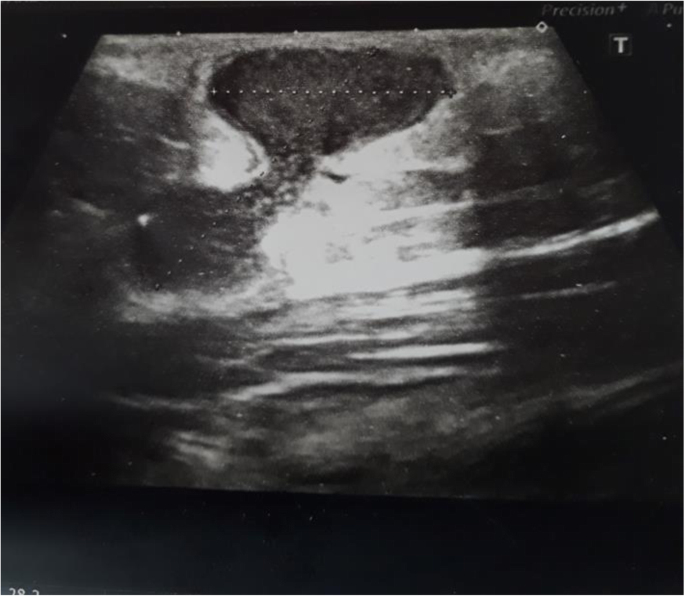

Complex abscess in the forearm of an IV drug user. Arm infection following an IV drug use. 23-year-old male with history of IV drug use and multiple admissions for infections.